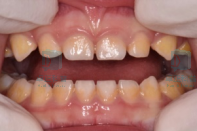

牙本质发育不全;

图片

牙本质发育不全是一种遗传性疾病,典型表现是牙齿呈琥珀色,容易出现广泛的磨耗、釉质剥脱,继而引起牙髓根尖周病变,因此早期发现、早期保护至关重要。如果发现孩子牙齿呈现出这种琥珀色改变,应尽早寻求专业儿童牙医的帮助。